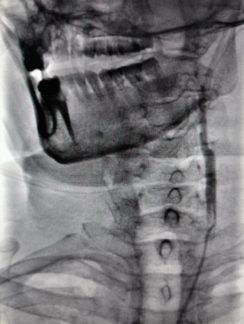

初始造影RICA起始位

病历夹什么径技·第152期|串联营病历夹:川陕大营_https://www.jmylbn.com_新闻资讯_第81张

初始造影后循环+LICA正位

病历夹什么径技·第152期|串联营病历夹:川陕大营_https://www.jmylbn.com_新闻资讯_第82张